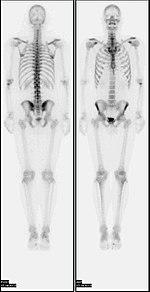

Bone scan showing multiple bone metastases from prostate cancer.

Some of the earliest investigations into skeletal metabolism were carried out by George de Hevesy in the 1930s, using phosphorus-32 and by Charles Pecher in the 1940s.[6][7]

In the 1950s and 1960s calcium-45 was investigated, but as a beta emitter proved difficult to image. Imaging of positron and gamma emitters such as fluorine-18 and isotopes of strontium with rectilinear scanners was more useful.[8][9] Use of technetium-99m (99mTc) labelled phosphates, diphosphonates or similar agents, as in the modern technique, was first proposed in 1971.[10][11]